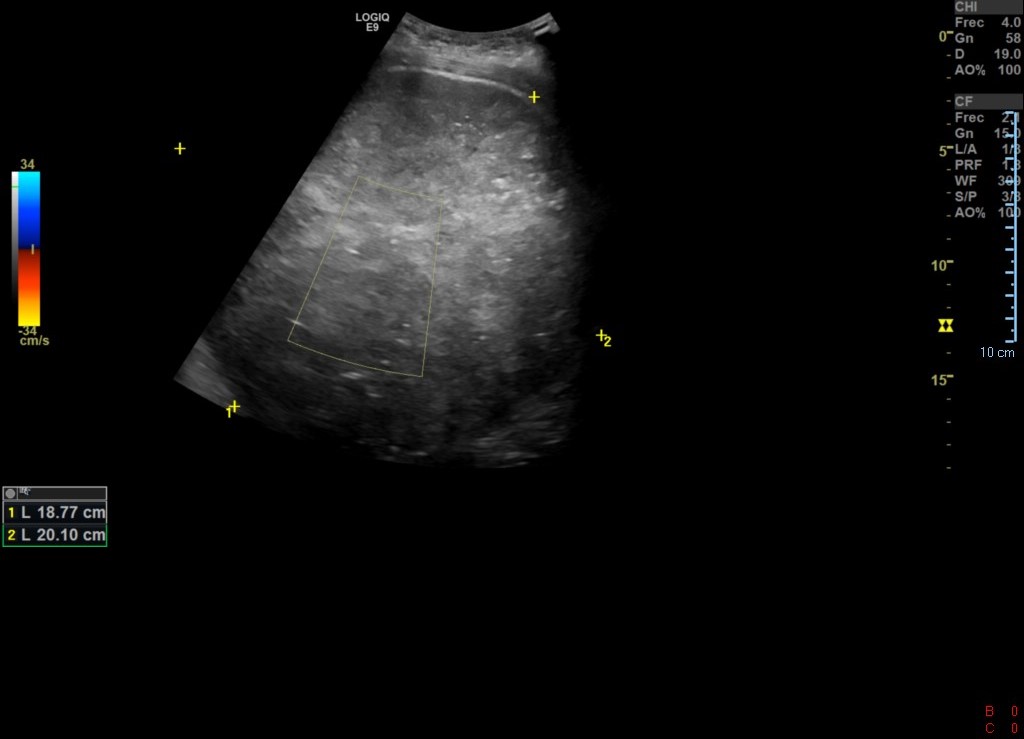

Ecografía de abdomen de Urgencias: se observa gran LOE pélvico abdominal ecogenicidad heterogénea, con hígado aumentado de tamaño y con imágenes hipoecoicas. Uterohidronefrosis derecha.

Igualmente se concluyó el estudio con ecografía de testículo y RNM.